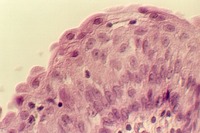

Stratified squamous epithelium

Stratified columnar/cuboidal epithelium